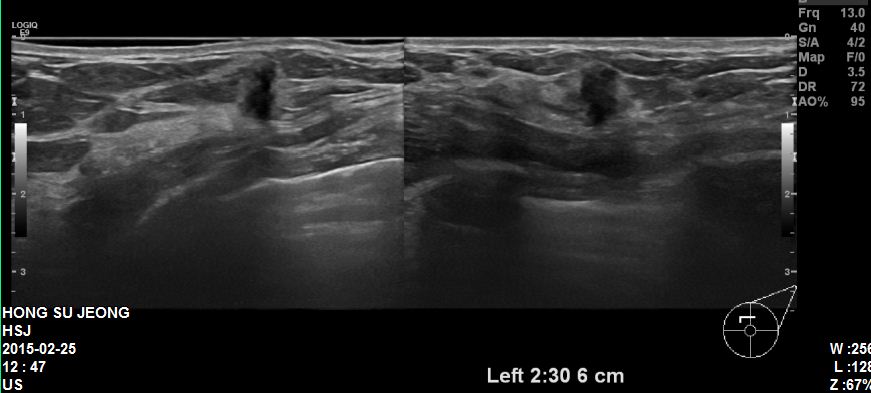

본원에 내원하신 40대 환자분이십니다.

좌측유방에 2시30분 방향에 혹 조직검사 시행하였고

결과상 침윤성유관암 진단되었습니다.